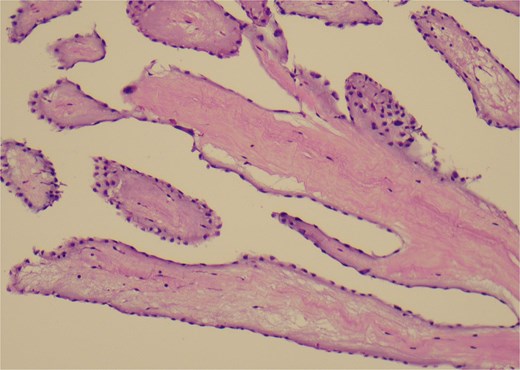

The patient underwent surgical excision of the LVOT mass via a median sternotomy. Cardiopulmonary bypass (CBP) was established using arterial cannulation in the ascending aorta and single, two-stage venous cannulation via the right atrium. An oblique aortotomy was performed to access the LVOT, and the mass was completely excised. The aorta was closed with 4–0 Prolene, and the excision site was inspected to ensure no residual tissue. Hemostasis was achieved, and CBP was weaned off once adequate cardiac function was confirmed. Two tube drainages in pericardial and mediastinal spaces. The pericardium was closed, with a total CBP time of 45 min, an aortic cross-clamp time of 27 min, and a total operative time of 3 h and 12 min. Gross pathology showed a 1 × 1 × 0.3 cm irregular, soft, grey-white polypoid mass. Histology examination of the mass revealed multiple branching papillary fronds with a central avascular collagen, lined by a layer of hyperplastic epithelial cells, consistent with papillary fibroelastoma (Figs 3 and 4).

A histological view of the excised mass reveals elongated and branching papillary fronds with central avascular collagen, lined by hyperplastic epithelial cells.